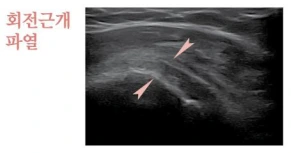

회전근개파열

2.PNG

회전근개는 어깨 안정성을 유지하는 매우 중요한 힘줄입니다. 회전근개는 어깨를 둘러싸는 극상근, 극하근, 견갑하근, 소원근의 네 개의 근육과 힘줄로 이루어져 있는데요. 회전근개가 고장 나면 어깨가 안정적으로 움직이기 어렵습니다. 보통은 파열이라고 하면 무조건 수술이 필요한 거라고 생각하시는데 90% 이상이 퇴행 변화에 의해서 생기기 때문에 충분히 비수술적 치료도 가능한 질환입니다.

팔을 들었다 내릴 때 통증이 발생하거나 삐걱하는 잡음이 생기는 증상이 대표적이고 중년 이후에 흔하게 발생할 수 있습니다. 퇴행성으로 천천히 진행될 수도 있지만, 증상이 오래 방치될 경우엔 오십견(유착성 동결견염) 증상을 동반하는 경우도 있으니 감별진단이 필수적입니다. 그럼 감별진단은 무엇으로 할까요? 어깨 인대는 일반적으로 엑스레이에는 나오지 않아서 MRI를 찍는 것이 일반적이었는데 최근 들어서는 초음파를 이용한 근골격계 초음파의 발달로 비수술적 진단 및 치료가 매우 쉬워졌으니 참고해주세요.